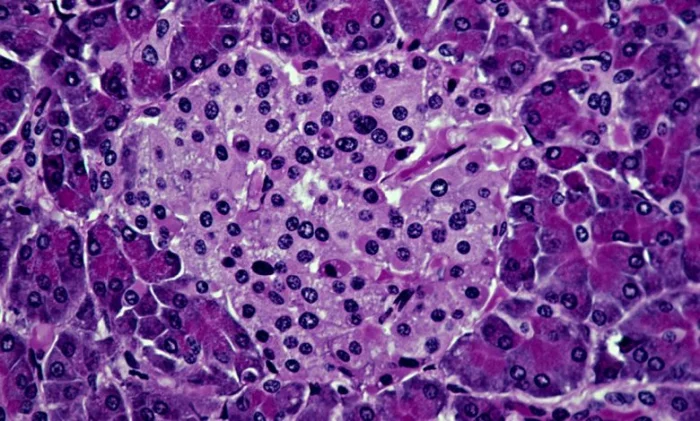

Исследователи из Медицинской школы Стэнфорда, стоящие за этой работой, полагают, что такой же подход может оказаться успешным и для людей. Болезнь возникает из-за сбоя в работе собственной иммунной системы организма, которая атакует производящие инсулин бета-клетки островков поджелудочной железы. В ходе эксперимента иммунную систему мышей перед трансплантацией подготовили с помощью ингибитора иммунитета, низкой дозы радиации и специально подобранных антител. Затем животным пересадили комбинацию кроветворных стволовых клеток и островковых клеток от другого животного.

В результате пересаженные клетки не были атакованы как чужеродные агенты, а иммунная система снова начала функционировать нормально. Учёные подчёркивают, что необходимо не только заместить утраченные островковые клетки, но и перезагрузить иммунную систему реципиента, чтобы остановить их дальнейшее уничтожение. Создание гибридной иммунной системы позволяет достичь обеих целей. Кроме того, ни у одной из мышей не развилась реакция «трансплантат против хозяина» — частое осложнение при пересадке клеток между людьми.